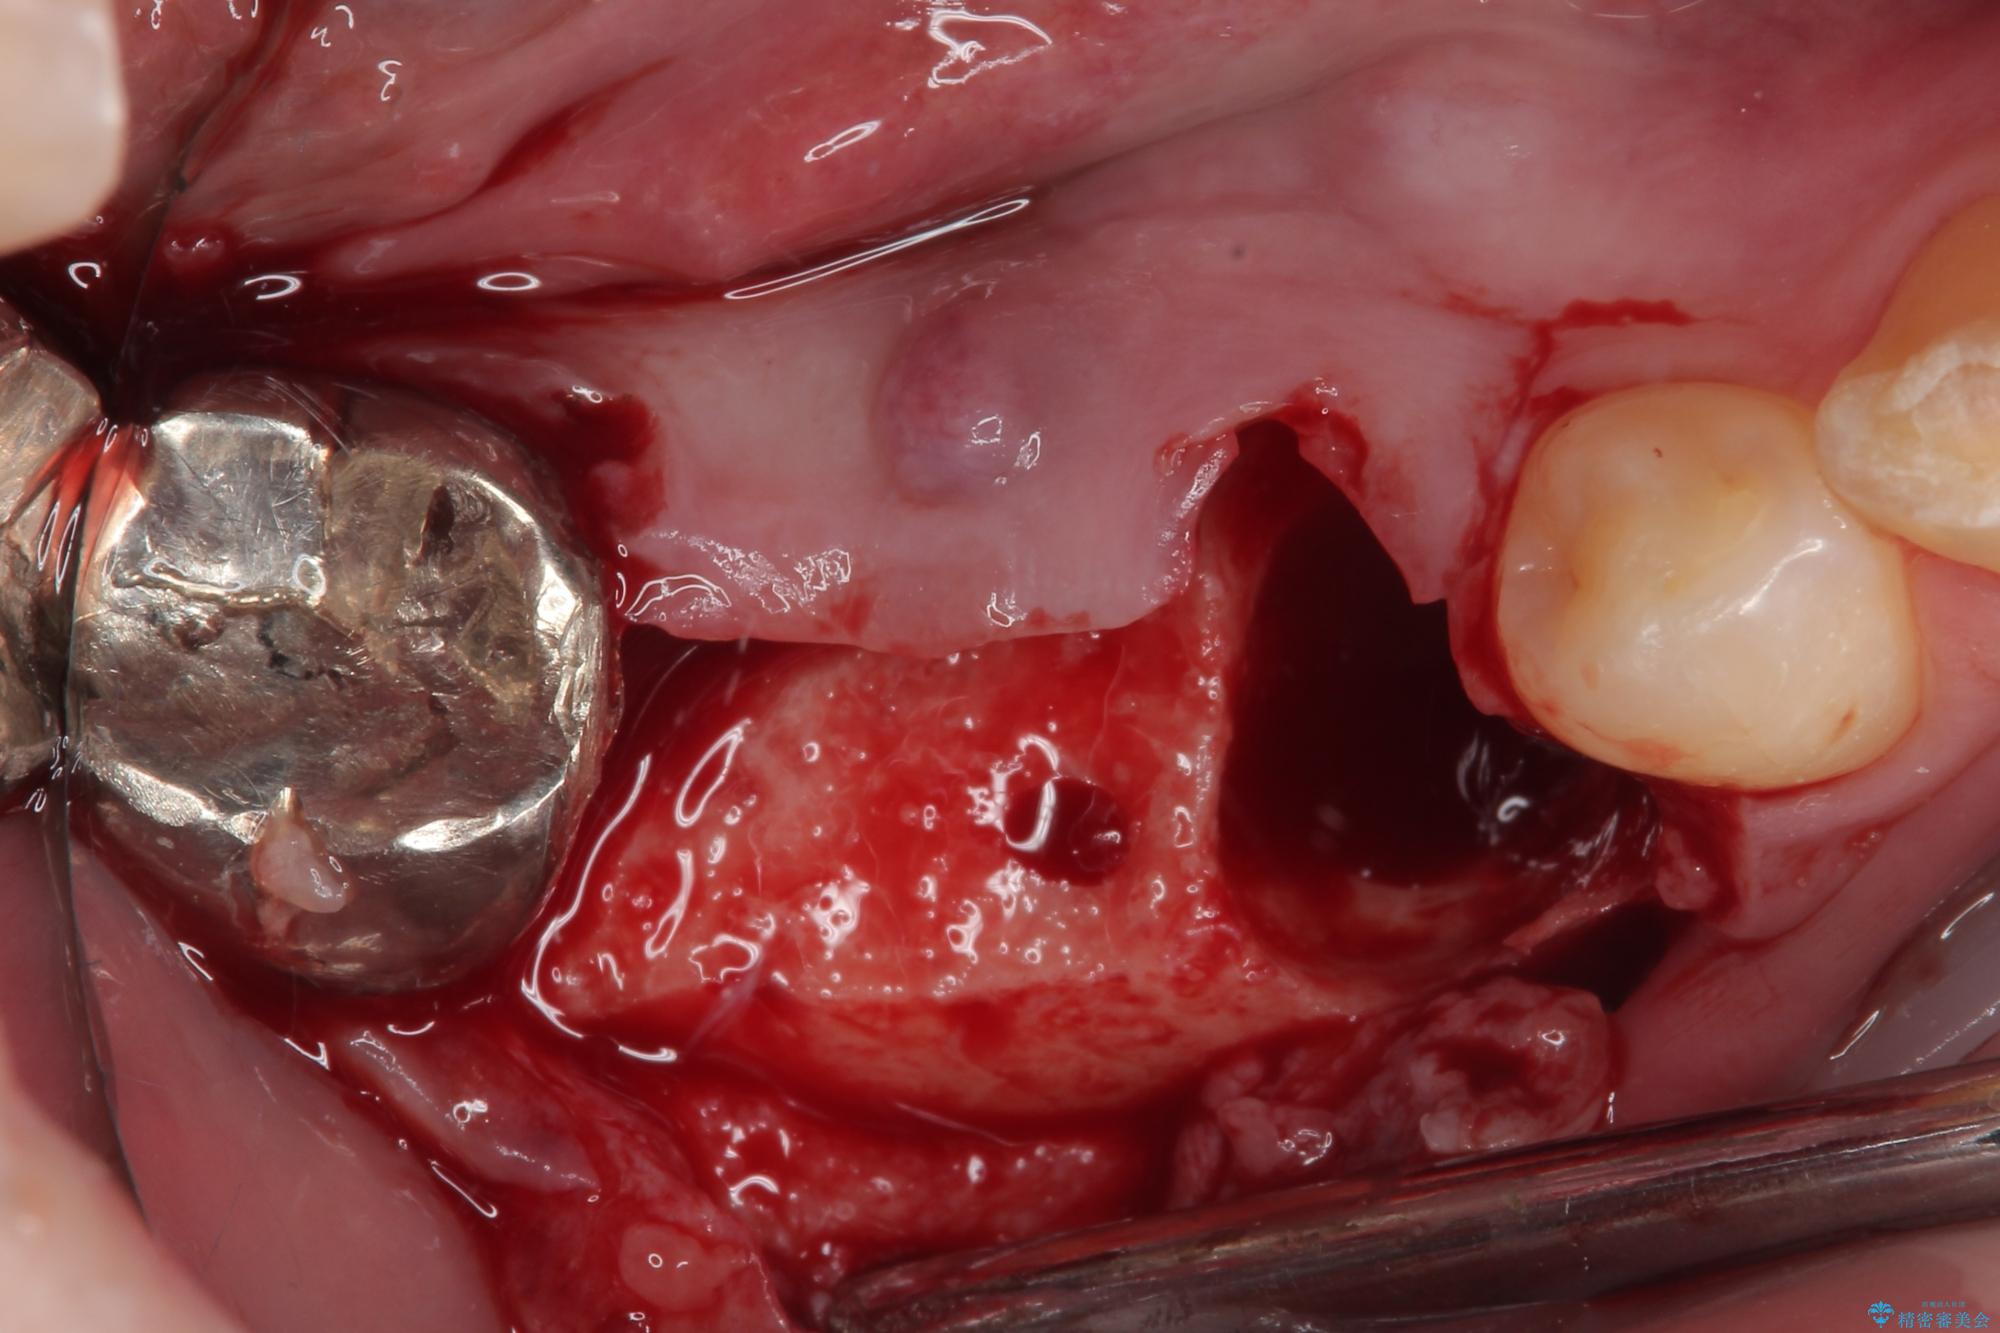

問題が起きていた手前の歯から膿が出てきたことを自覚して当院を来院されましたが、既に歯根破折をしており、抜歯が必要な状態でした。

咬合力が非常に強い患者様であり、2歯欠損のブリッジ(しかも大臼歯は失活歯)は歯根破折のリスクが高すぎると判断し、抜歯部および欠損部に対して、インプラントによる補綴治療を行うこととしました。